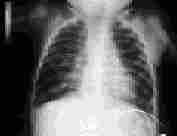

The incidence of bronchopulmonary dysplasia is decreasing as a result of the use of prophylactic surfactant replacement therapy.24 Bronchopulmonary dysplasia occurs primarily in infants with a history of hyaline membrane disease who required supplemental oxygen and mechanical ventilation (Figure 4). A family history of asthma does not increase the risk of bronchopulmonary dysplasia but is associated with more severe disease.25 With severe disease, chest radiography shows cystic lesions. In infants with bronchopulmonary dysplasia who continue to require oxygen after hospital discharge, an oxygen saturation of 94 to 95 percent promotes pulmonary vasodilation and reduces the risk of pulmonary hypertension. Infants receiving oxygen have better weight gain, better development and fewer intercurrent respiratory illnesses than infants with impaired oxygenation who are not treated with supplemental oxygen.

FIGURE 4.

Bronchopulmonary dysplasia in an eight-month-old child with hyperexpansion of the lungs and diffuse fibrosis.